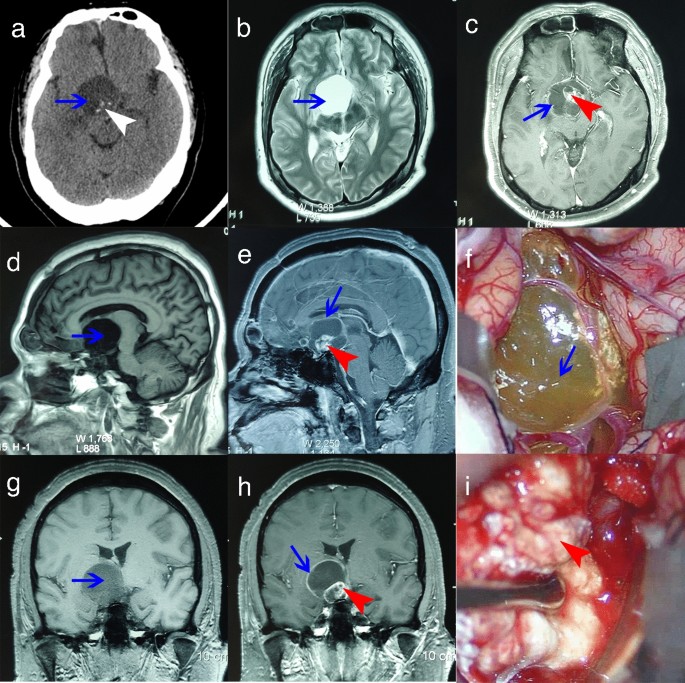

Imaging characteristics of ACP cyst wall and intraoperative material collection

CT scans (from case 6) of ACP showed a low-density cystic component and a high-density calcified solid component (Fig. 1a). Under MRI (from case 6), the cystic component of the T1 sequence showed a low signal (Fig. 1d, g), and the cystic component of the T2 sequence showed a high signal (Fig. 1b). Under enhanced scanning, the cyst wall and the solid component produced obvious enhanced signals (Fig. 1c, e, h). During the operation, the cyst wall was seen as a translucent film with variable thickness and different degrees of adhesion to and invasion into the surrounding tissue (Fig. 1f). The solid tumor component was solid, tough, and mixed with hard calcifications (Fig. 1i). ACP imaging characteristics revealed that the cyst wall and the solid tumor component had a certain connection or continuity, and the cyst wall was likely to be tumor tissue that maintained continuity with the solid tumor component. During surgical resection, the cyst wall presented more difficulties than the solid tumor component.

Preoperative and intraoperative imaging of cyst wall and solid body. (a) CT scan shows low-density cystic lesion and high-density calcifications (blue arrow, cyst; white arrowhead, calcifications). (b) T2-weighted axial MRI shows hyperintense signal lesion (blue arrow: cyst). (c,e,h) T1-weighted enhanced MRI shows the peripheral cyst wall and heterogeneous solid body (blue arrow, cyst wall; red arrowhead, solid body). (d,g) T1-weighted MRI shows hypointense signal lesions (blue arrow: cyst). (f,i) Cyst wall and solid body during operation (blue arrow, cyst wall; red arrowhead, solid part).